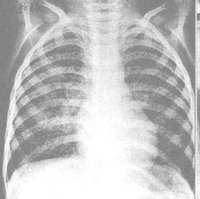

血行播散型肺結核急性粟粒型結核是急性全身血行播散型結核病的一部分,起病急,有全身毒血症狀,常伴髮結核性腦膜炎,X線顯示雙肺在濃密的網狀陰影上,滿布境界清晰的粟粒狀陰影,直徑約2mm,大小及密度大體相等。病初胸片可能無明顯粟粒狀影,或僅僅有關瀰漫性網狀改變易誤診為傷寒、敗血症等其他發熱性疾病。若人體抵抗力較強,少量結核菌分批經血液循環進入肺部,其血行播散灶常大小不均勻、新舊不等,在雙肺上中部分部呈對稱性分布,稱為亞急性過慢性血行播散型肺結核。其病情發展緩慢,通常無顯著中毒症狀,患者可無自覺症狀,偶於X線檢查時才被發現。此時病灶較穩定或已硬結癒合。

2、影像學檢查胸部X線檢查可以發現肺內病變的部位、範圍,有無空洞或空洞大小,洞壁厚薄等。X線對各類結核病變的透過度不同,通過X線檢查大致能估計結核病灶的病理性質,並能早期發現肺結核,以及判斷病情發展及治療效果,有助於決定治療方案。必須指出,不同病因引起的肺內病變,可能呈現相似的X線影像,故亦不能僅憑X線檢查輕易確定肺結核的診斷。X線攝片結合透視有助於提高診斷的準確性,可發現肋骨、縱隔、膈肌或被心臟遮蓋的細胞病灶,並能觀察心、肺、膈肌的動態。肺結核的X線表現包括:纖維鈣化的硬結病灶,表現為密度較高、邊緣清晰的斑點、條索取或者結節;浸潤性病灶,表現為密度較單,邊緣模糊的雲霧狀陰影;乾酪樣病灶,表現為密度較高,濃淡不一,有環形邊界透光區的空洞等。肺結核病灶通常在肺上部、單側或雙側,促成時間較長,且有多種不同性質的病灶混合存在及肺內播散跡象。凡X線胸片上顯示滲出性或滲出增殖性病灶、乾酪樣肺炎、乾酪樣病灶、空洞(除淨化空洞外),均提示為活動性病變;增殖性病變、纖維包裹緊密的乾酪硬結灶火及纖維鈣化灶等,均屬非活動性病變。活動性病灶的痰中仍可找到結核菌。由於肺結核病變多為混合性,在未達到完全增殖或纖維鈣化時,均仍應考慮為活動性。肺部CT檢查對於發現微小或隱蔽性病變,了解病變範圍及肺病變鑑別等方面均有幫助。

4.x 線胸片兩肺見典型粟粒陰影 。胸CT急性血行播散型肺結核表現為直徑1-3mm大小、密度及分布均勻的粟粒結節;而亞急性和慢性患者表現以上中肺野為主的3-7mm大小、密度及分布不均勻的結節。結節的邊界多數尚清晰,但也有表現邊界模糊;結節隨機分布於肺小葉、小葉間隔及胸膜下。